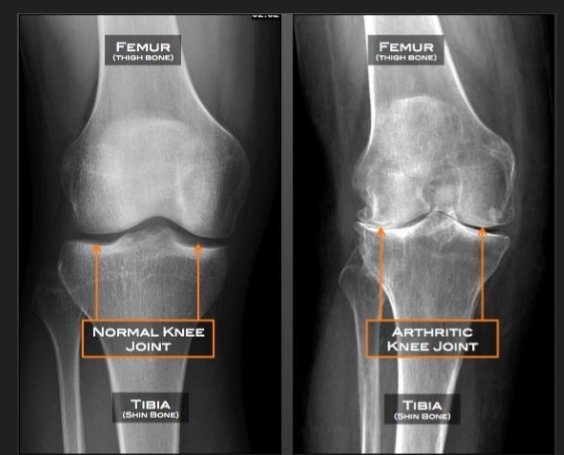

• X-rays, which can show bone and cartilage damage as well as the presence of bone spurs

MRI scans may be ordered when X-rays do not give a clear reason for joint pain or when the X-rays suggest that other types of joint tissue could be damaged. Doctors may use blood tests to rule out other conditions that could be causing the pain, such as rheumatoid arthritis, a different type of arthritis caused by a disorder in the immune system.